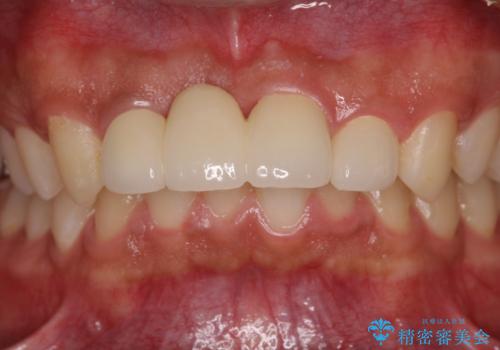

転んでぶつけて抜歯 前歯のオールセラミックブリッジ

抜歯後の欠損部はブリッジにて補綴治療を行うこととしました。

事故直後のレントゲン写真では全ての歯の根尖部に骨透過像が認められましたが、治療後には全ての透過像がなくなっていました。

診断に2-3ヶ月かかりましたが、的確に診断を行うことができました。